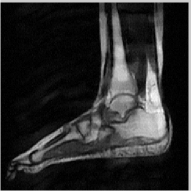

The reconstructions of an ankle image from its 4 fold Cartesian undersampled Fourier data, corrupted with zero mean complex Gaussian noise with a standard deviation σ=10𝜎10\sigma=10, are shown in Fig. 5. This is a really challenging case since the 1-D downsampling pattern is considerably less efficient than the 2-D random pattern used in the previous experiment. We observe that the non-local algorithm provides better reconstructions than the other schemes. Specifically, the TV scheme results in patchy artifacts. The DLMRI scheme results in blurring and loss of details close to the heel. The details are relatively better preserved close to the finger since there are no structures above or below it that aliases to it. By contrast to the classical algorithms, the degradation in performance of the non-local algorithm is comparatively small. The quantitative comparisons of the algorithms on this setting using different images are shown in the top section of Table IV.

Figure 5: Comparison of the algorithms in the presence of noise. We consider the recovery of a 256×256256256256\times 256 MRI ankle image from its Cartesian Fourier sampling pattern (shown in (e)), contaminated by zero mean complex Gaussian noise with standard deviation σ=10𝜎10\sigma=10. The top row shows the original and reconstructed images, while the error images scale by a factor of five are shown in the bottom row. This is a challenging case due to the high 1-D undersampling factors and noise. We observe that the NLS scheme provides the best reconstructions with minimal alias artifacts.